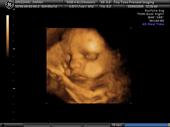

<3 Waiting on my Miracle : ) profile picture

&lt;3 Waiting on my Miracle : )